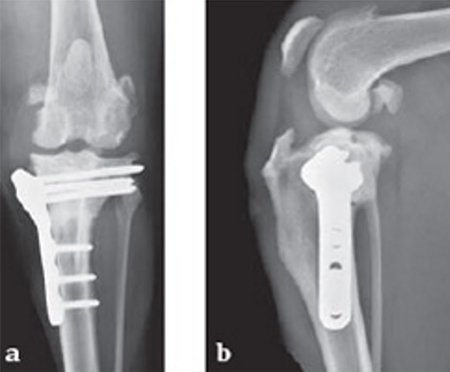

The stifle joint was surgically explored. All remaining remnants of the torn cranial cruciate ligament were debrided; in addition, the caudal pole of the medial meniscus was torn/crushed, and a partial meniscectomy of the damaged portion was performed. A TPLO plate 3.5 was applied to stabilize the fracture. The plate was applied in a neutral fashion. Postoperative x-rays revealed a tibial plateau angle of 5, and a correction of the torsion to 0 mm.

Follow-up x-rays at 8 weeks postoperatively revealed that the osteotomy had healed, and the dog was doing very well. The identical procedure was performed on the opposite stifle joint 2 months later. Healing was again obtained 8 weeks postoperative. Presently, the dog is about 1 year postoperatively and functioning very well.